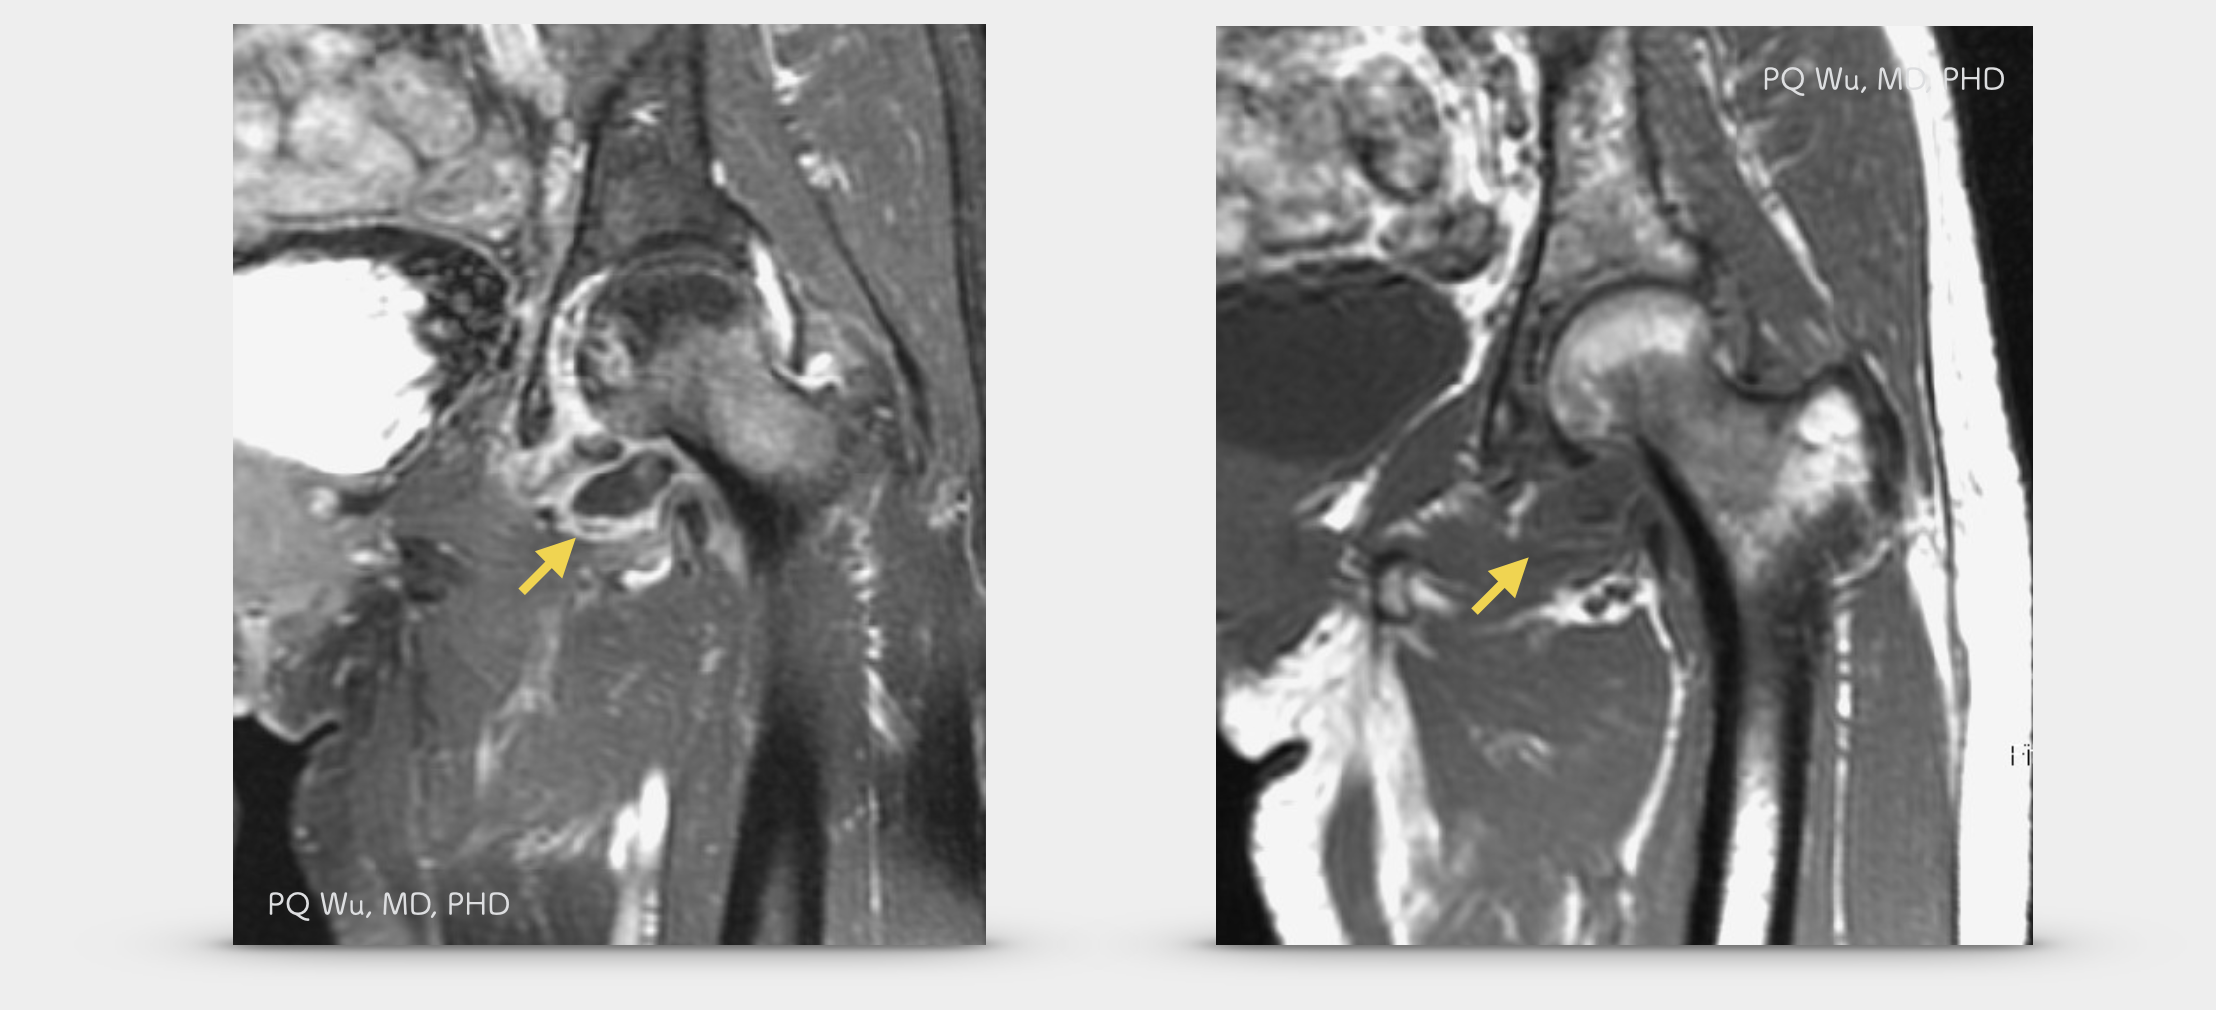

在MRI的影像之中,腱鞘巨細胞瘤最大的特色,便是腫瘤中因為富含大量的血鐵素(hemosiderin),因此在T1與T2訊號中,均會呈現特殊的低訊號,這個特色,使用來區分腱鞘巨細胞瘤與其他的良性或是惡性腫瘤的重要指標。以下為一位46歲男性膝蓋腱鞘巨細胞瘤的影像學表現:

58歲女性,左髖腱鞘巨細胞瘤(MRI)